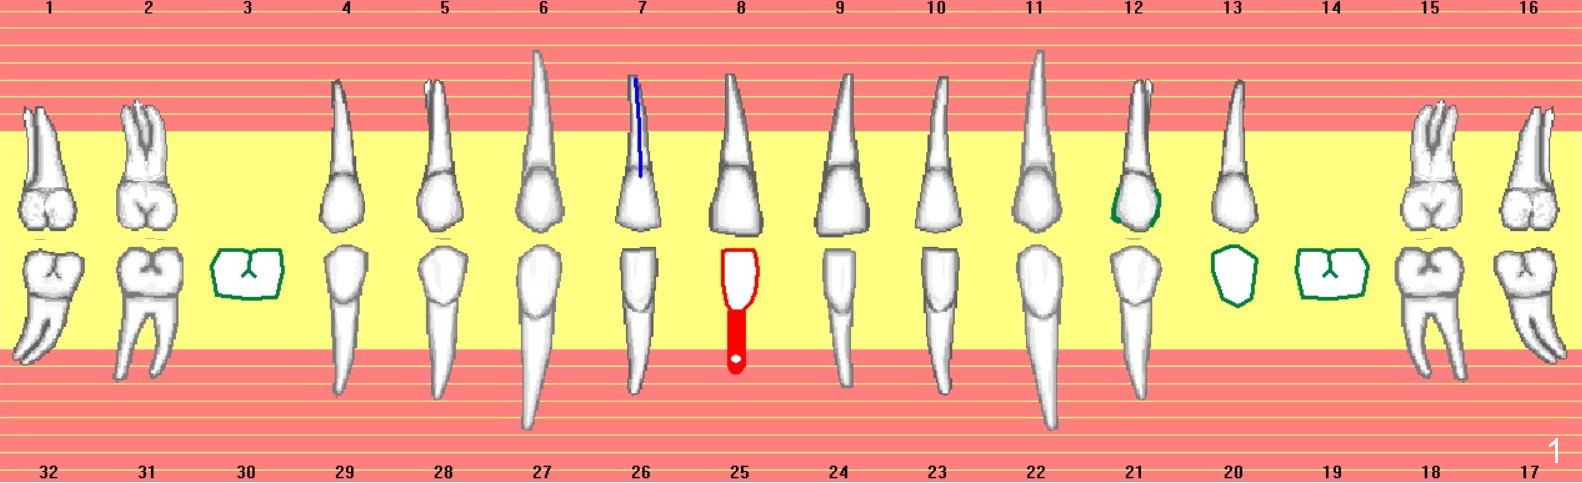

A 53-year-old woman (WX) had several missing teeth with a lower flipper (Fig.1,2, conditions 2 years ago). Recently the tooth #24 fractured equigingival (Fig.2 saw-toothed line). The edentulous area at #25 is narrow buccolingually (Fig.4a). Start osteotomy lingually (L, Fig.4b red circle). As the osteotomy increases (Fig.4c red circle) and a 2 or 2.5 mm 1-piece DIO implant is placed (Fig.4d green circle), the weaker buccal (B) plate is being expanded buccally.

A 3 or 3.5 mm 1-piece implant is placed at #24 (Fig.3) after Metronidazole socket soaking. The larger one is chosen (3.5 mm (Tatum)) if the implant at #25 fails to be placed. A dummy implant is placed partially to test trajectory. If the latter is bad, use an angled 1-piece one (Tatum). The composite overhang (Fig.2 *) is to be trimmed (Fig.3 red line). Take preop photos to show the concave buccal plate (Fig.4a) and intra- and post-op ones to show bone expansion (Fig.4b-d).